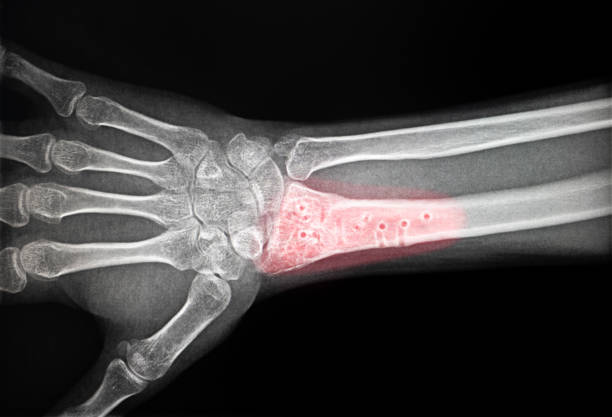

골다공증을 진단하는 가장 일반적인 시스템은 이진 에너지 X선 흡수 측정법(DEXA 또는 DXA)과 유사한 뼈 점도 검사입니다. 이 검사는 몸의 다채로운 부위에서 뼈의 점도, 일반적으로 엉덩이와 척추를 측정하고 그 결과를 젊고 건강한 성인의 평균 뼈 점도와 비교합니다. 점수가 낮을수록 뼈가 약해지고 골절의 위험이 증가한다는 것을 나타냅니다. 이러한 검사는 골다공증을 조기에 발견하고 운영하는 데 매우 중요합니다. 골다공증이 있는 개인의 골절 책임을 예측하는 데 도움이 되는 여러 위협 평가 도구를 사용할 수 있습니다. 유사한 도구 중 하나는 FRAX(골절 위험 평가 도구)인데, 나이, 코이투스, 체중, 키, 이전 골절, 골다공증 가족력, 생활 습관(예: 흡연, 알코올 섭취)과 유사한 요소를 고려하여 엉덩이 골절 또는 주요 골다공증 골절의 10가지를 추정합니다. 이러한 도구는 의료 제공자가 치료 및 운영 전략에 대해 정보에 입각한 의견을 내는 데 도움이 됩니다. 뼈 점도 검사 외에도 혈액 검사는 칼슘, 비타민 D 및 기타 뼈 발달 라벨의 상황을 측정하는 데 사용될 수 있습니다. C-말단 텔로펩티드(CTX) 또는 N-말단 텔로펩티드(NTX)와 유사한 뼈 흡수 라벨의 상승된 상황은 뼈 손실 증가를 나타낼 수 있습니다. 이러한 테스트는 골다공증의 경직성을 평가하고 치료 개입의 효과를 커버하는 데 도움이 됩니다.